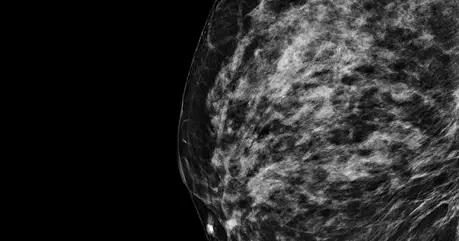

Bi-Rads C

The breast tissue is mostly fibroglandular tissue with some areas of fatty tissue. The breast tissue is dense.